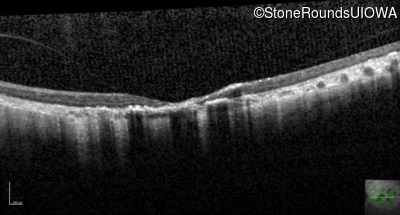

Optical Coherence Tomography - Right - 20/200 sc

Exemplar / OCT Stack

OCT Stack